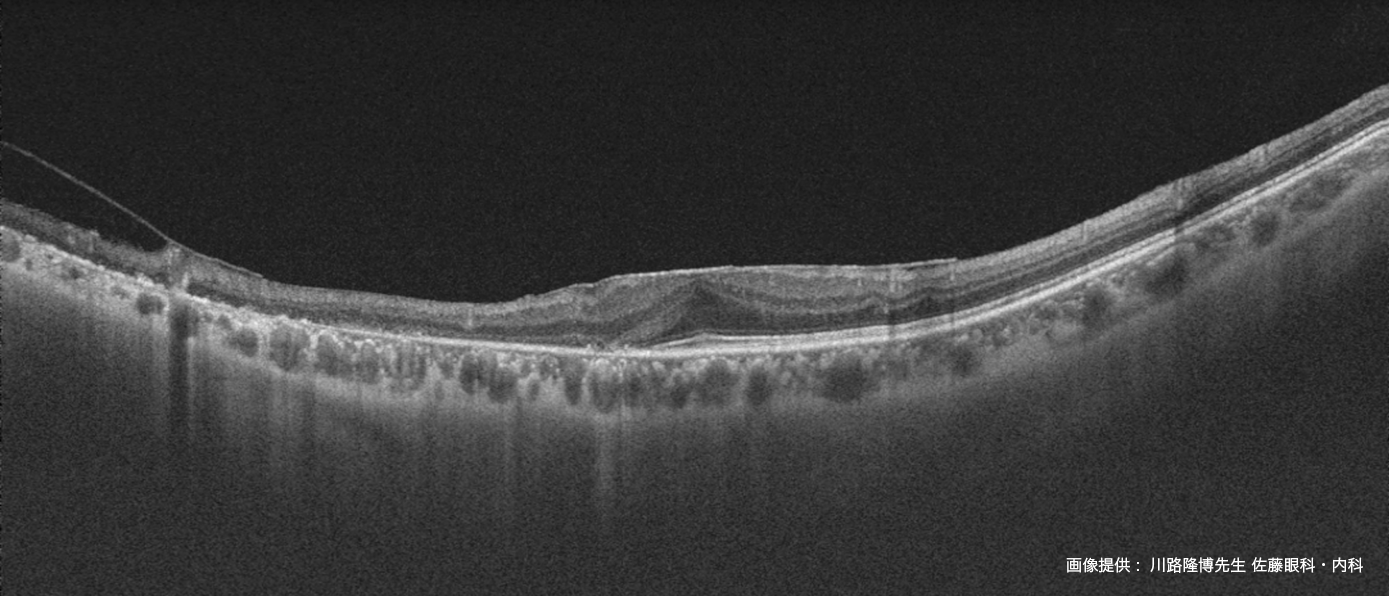

信頼性の高いSwept-Source OCTは12mmの広範囲撮影において

デノイズ効果を発揮し、さらに見やすい画像を提供します。

診断に有用な撮影機能を集約 - 白内障や硝子体混濁のある疾患眼に対しても鮮明なOCT 像を表示

DRI OCT Triton シリーズにトプコン独自のアルゴリズムOCT Angiography Ratio Analysis = OCTARA™を搭載したことで、

脈絡膜レベルの血流まで高感度、高侵達に画像化します¹。トプコン独自のアルゴリズムOCTARA は、

同じ断面で撮影された複数のOCT 画像から血管内の血流の様子を画像化する技術です。弱い信号変化でも高感度で画像化できるため、

毛細血管の観察など臨床に活用されています。